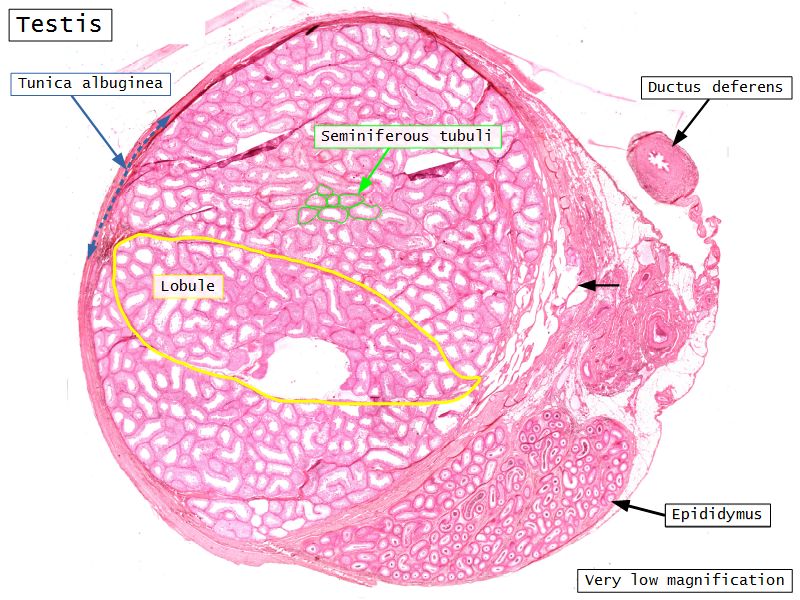

Testis

Slide 84

Testis

- Tunica albuginea

- Lobuli

- Seminiferous tubuli

- Epididymus

- Ductus deferens

Tunica albuginea

- Thick fibrous CT capsule

- Forms septae

- Divide testis into lobuli

Lobuli

- Pyramidal shaped compartments

- Contain 1 - 4 seminiferous tubules each within

- Meshwork of loose CT

- AVN

- Leydig cells

Leydig cells

- Interstitial cells

- Surrounded by rich AVL

- Large round - polygonal shape with clear cytoplasm

- Large central nucleus

- Endocrine - testosterone

Seminiferous tubuli

- Site of spermatozoa production

- 150 - 250 µm diameter

- Complex stratified epithelium

- Blood-testis barrier